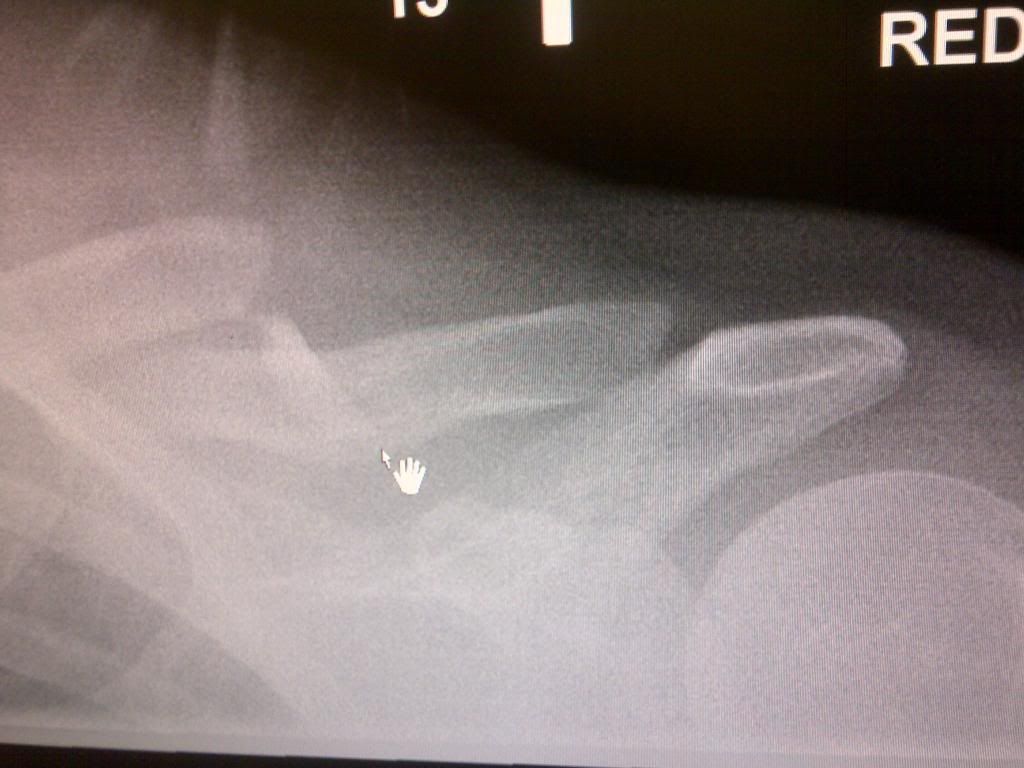

Fracture Collarbone Recovery Time . It is recommended that you. Falls, such as falling onto the shoulder or onto an outstretched arm. Bone healing usually takes 3 to 6 weeks for. the time for a broken collarbone to fully heal depends on the severity of the injury. the second thing that helps in the treatment of clavicle fractures is pain relief with cold therapy and pain medication. Clavicle fracture recovery times can vary,. how long does it take to recover from a broken collarbone? Clavicle fracture (broken collarbone) a clavicle fracture is a break in the collarbone, one of the main bones in the shoulder. Children often recover quicker, usually in 3 to 4 weeks. healing times vary depending on the individual fracture. most people recover from a broken collarbone in 6 to 8 weeks. people who have a broken collarbone usually need to wear a sling. Common causes of a broken collarbone include: In the first four to six weeks, you shouldn’t lift anything.

Fracture Collarbone Recovery Time Children often recover quicker, usually in 3 to 4 weeks. Clavicle fracture recovery times can vary,. the time for a broken collarbone to fully heal depends on the severity of the injury. Clavicle fracture (broken collarbone) a clavicle fracture is a break in the collarbone, one of the main bones in the shoulder. Common causes of a broken collarbone include: Children often recover quicker, usually in 3 to 4 weeks. how long does it take to recover from a broken collarbone? Bone healing usually takes 3 to 6 weeks for. the second thing that helps in the treatment of clavicle fractures is pain relief with cold therapy and pain medication. It is recommended that you. In the first four to six weeks, you shouldn’t lift anything. healing times vary depending on the individual fracture. most people recover from a broken collarbone in 6 to 8 weeks. Falls, such as falling onto the shoulder or onto an outstretched arm. people who have a broken collarbone usually need to wear a sling.